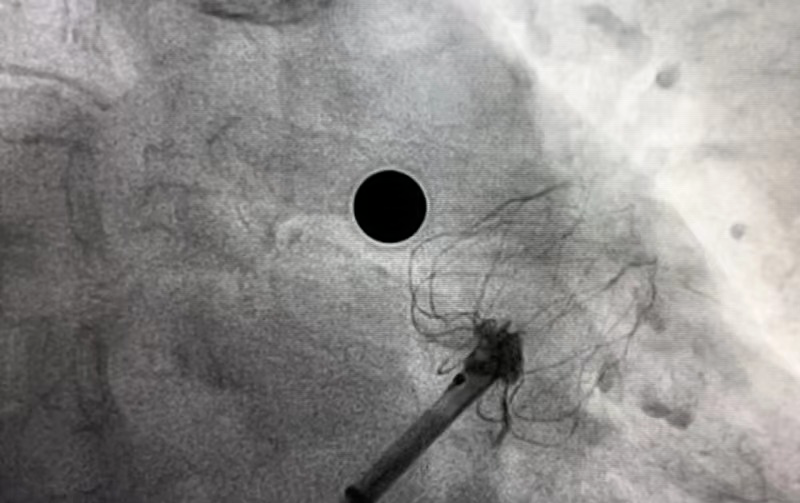

在團隊緊密配合下,謝桂庭巧妙地將封堵器坐落到心耳上緣囊袋,同時施加逆時針的力減少下緣露肩。緩慢平穩展開,一次到位,實現平口封堵。在DSA下進行牽拉實驗,封堵器回彈明顯無位移,提示穩定性良好。左心耳封堵器無露肩,無殘余分流,壓縮比13%-25%,滿足PASS原則評估,釋放封堵器。